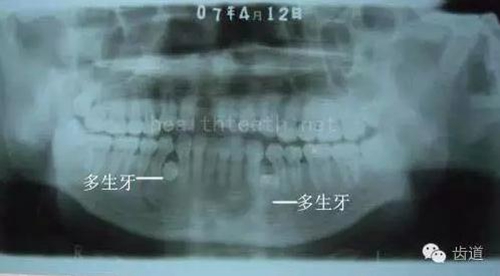

3、多生牙

病例1

47.jpg

48.jpg

49.jpg

病例3,同時(shí)多生兩顆牙齒

52.jpg